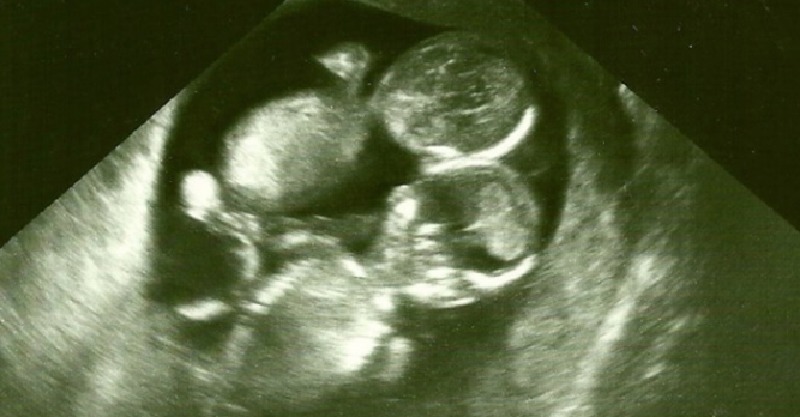

一位有著難以受孕體質的澳洲女子喜懷雙胞胎讓她興奮不已!沒想到醫師下一刻的沉重發言卻讓她再次跌落穀底...到底怎麼回事呢?

這名澳洲女子叫做凱特,因為有著難以受孕體質,和老公領養了2個小孩,但還是希望有自己的孩子。直到有一天醫生宣告她懷孕了,而且還是雙胞胎,讓她簡直不敢相信!

正當凱特喜出望外,醫生卻發現了另一個沉重事實,凱特所懷的雙胞胎是機率只有1%的「MoMo寶貝」,也就是「單羊膜雙胞胎」,這樣的雙胞胎因為共用一個羊膜,胚胎極有可能會發展成連體嬰,也容易因為沒有薄膜隔閡造成臍帶纏繞,導致胎兒缺氧的狀況,存活率只有正常雙胞胎的一半,正因如此,醫生建議凱特先不要對外公開懷孕消息。